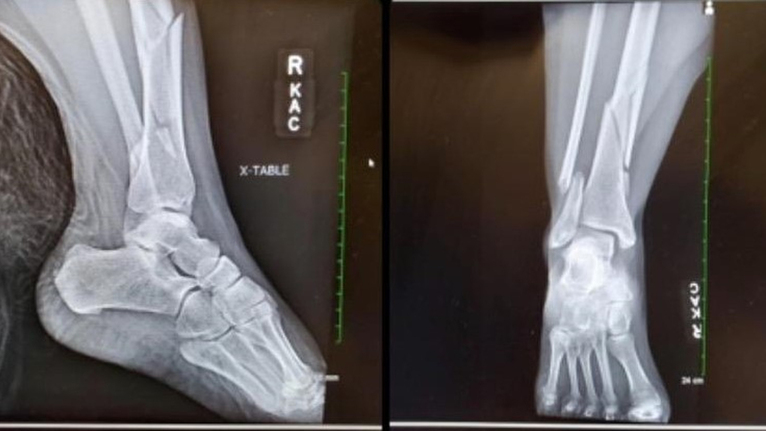

It wasn’t until later she learned that her foot rotated so much that it broke her tibia (shinbone), fibula (runs parallel to the shinbone) and ankle.

The emergency medicine staff immediately took X-rays, and it was clear that due to the severity of the breaks in her lower leg and ankle, Jacqui would undoubtedly need surgery.

“Jacqui’s injury was severe because not only was it a break at her ankle that needed surgery, but she also broke her tibia which made her leg unstable,” Dr. Dixon explained. “She required a nail that was placed inside her tibia to fix the leg, and then plates and screws to stabilize her ankle.”